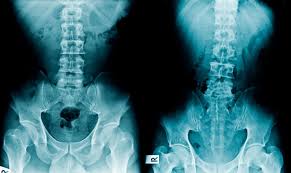

Spinal stenosis occurs if your spinal canal narrows and puts more pressure on the nerves in. A diagnosis of degenerative disc disease may be alarming at first as it sounds like a progressive degenerative disease. DelveInsights Degenerative Disc Disease DDD Market Insights Epidemiology and Market Forecast 2030 report delivers an in-depth understanding of the historical and forecasted epidemiology as well as the Degenerative Disc Disease DDD Market Size and Share in the United States EU5 Germany Spain Italy France and United Kingdom and Japan. Degenerative Disc Disease Xray In its most basic form degenerative disc disease also known as DDD is the pain weakness or potential numbness that stems from a degenerated disc in the spine. Specifically it is a condition where the discs between vertebrae lose cushioning causing them to fragment and herniate. Degenerative disc disease is a common disability among Veterans. Spine conditions are usually rated based upon how limited your back or neck range of motion is.